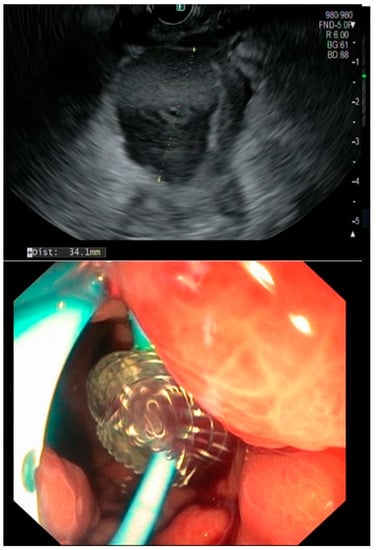

In detail, a total of 22 patients (36.6%) had a resolution of pancreatic fistulas with conservative management including a secondary percutaneous drainage within 29 days (median, IQR 13–58). Another 13 cases (21.7%) were treated simultaneously with transpapillary pancreatic stenting, as shown in Table 4. When transpapillary stenting was started, PCD was either removed at the time of stent placement or two to four weeks after the procedure. Transpapillary stents were removed 12 weeks after ERCP.

In this patient cohort, the treatment strategy was changed in case of fistula persistence after 4–6 weeks following one intervention. If PCD resulted in an ongoing collection, EUS-guided transmural stenting was performed if technically possible prior to placing a transpapillary stent after sphincterotomy (in case of left-sided resection). If fluid collections were not accessible via EUS, patients received an ERCP. Pancreatic stent replacement was then performed every 3 months or, in case of resolution, removed. Short-term imaging controls helped to adjust the treatment course and EUS drainage added when possible (Figure 3).

Figure 3. Radiograph of a pancreatic fistula during ERCP and transpapillary stenting.